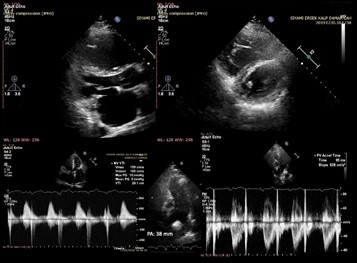

Yapılan transtorasik ekokardiyografisinde; parasternal uzun aks görüntülemede posterior mitral leaflette sütur anuloplastiye baÄŸlı hareket kısıtlılığı, dilate sol atrium görüntülenmekte olup kısa aks görüntülerde sistolde daha belirgin olmak üzere basınç ve volüm yükünü temsil eden “D-shaped” görünüm mevcut. Posterior leafletteki anuloplastiye baÄŸlı hafif mitral darlık fizyolojisi mevcut. Pulmoner arter çapı 38 mm ve dilate. Akselerasyon zamanı kısalmış olarak izlendi (Resim-2).

Resim-2: